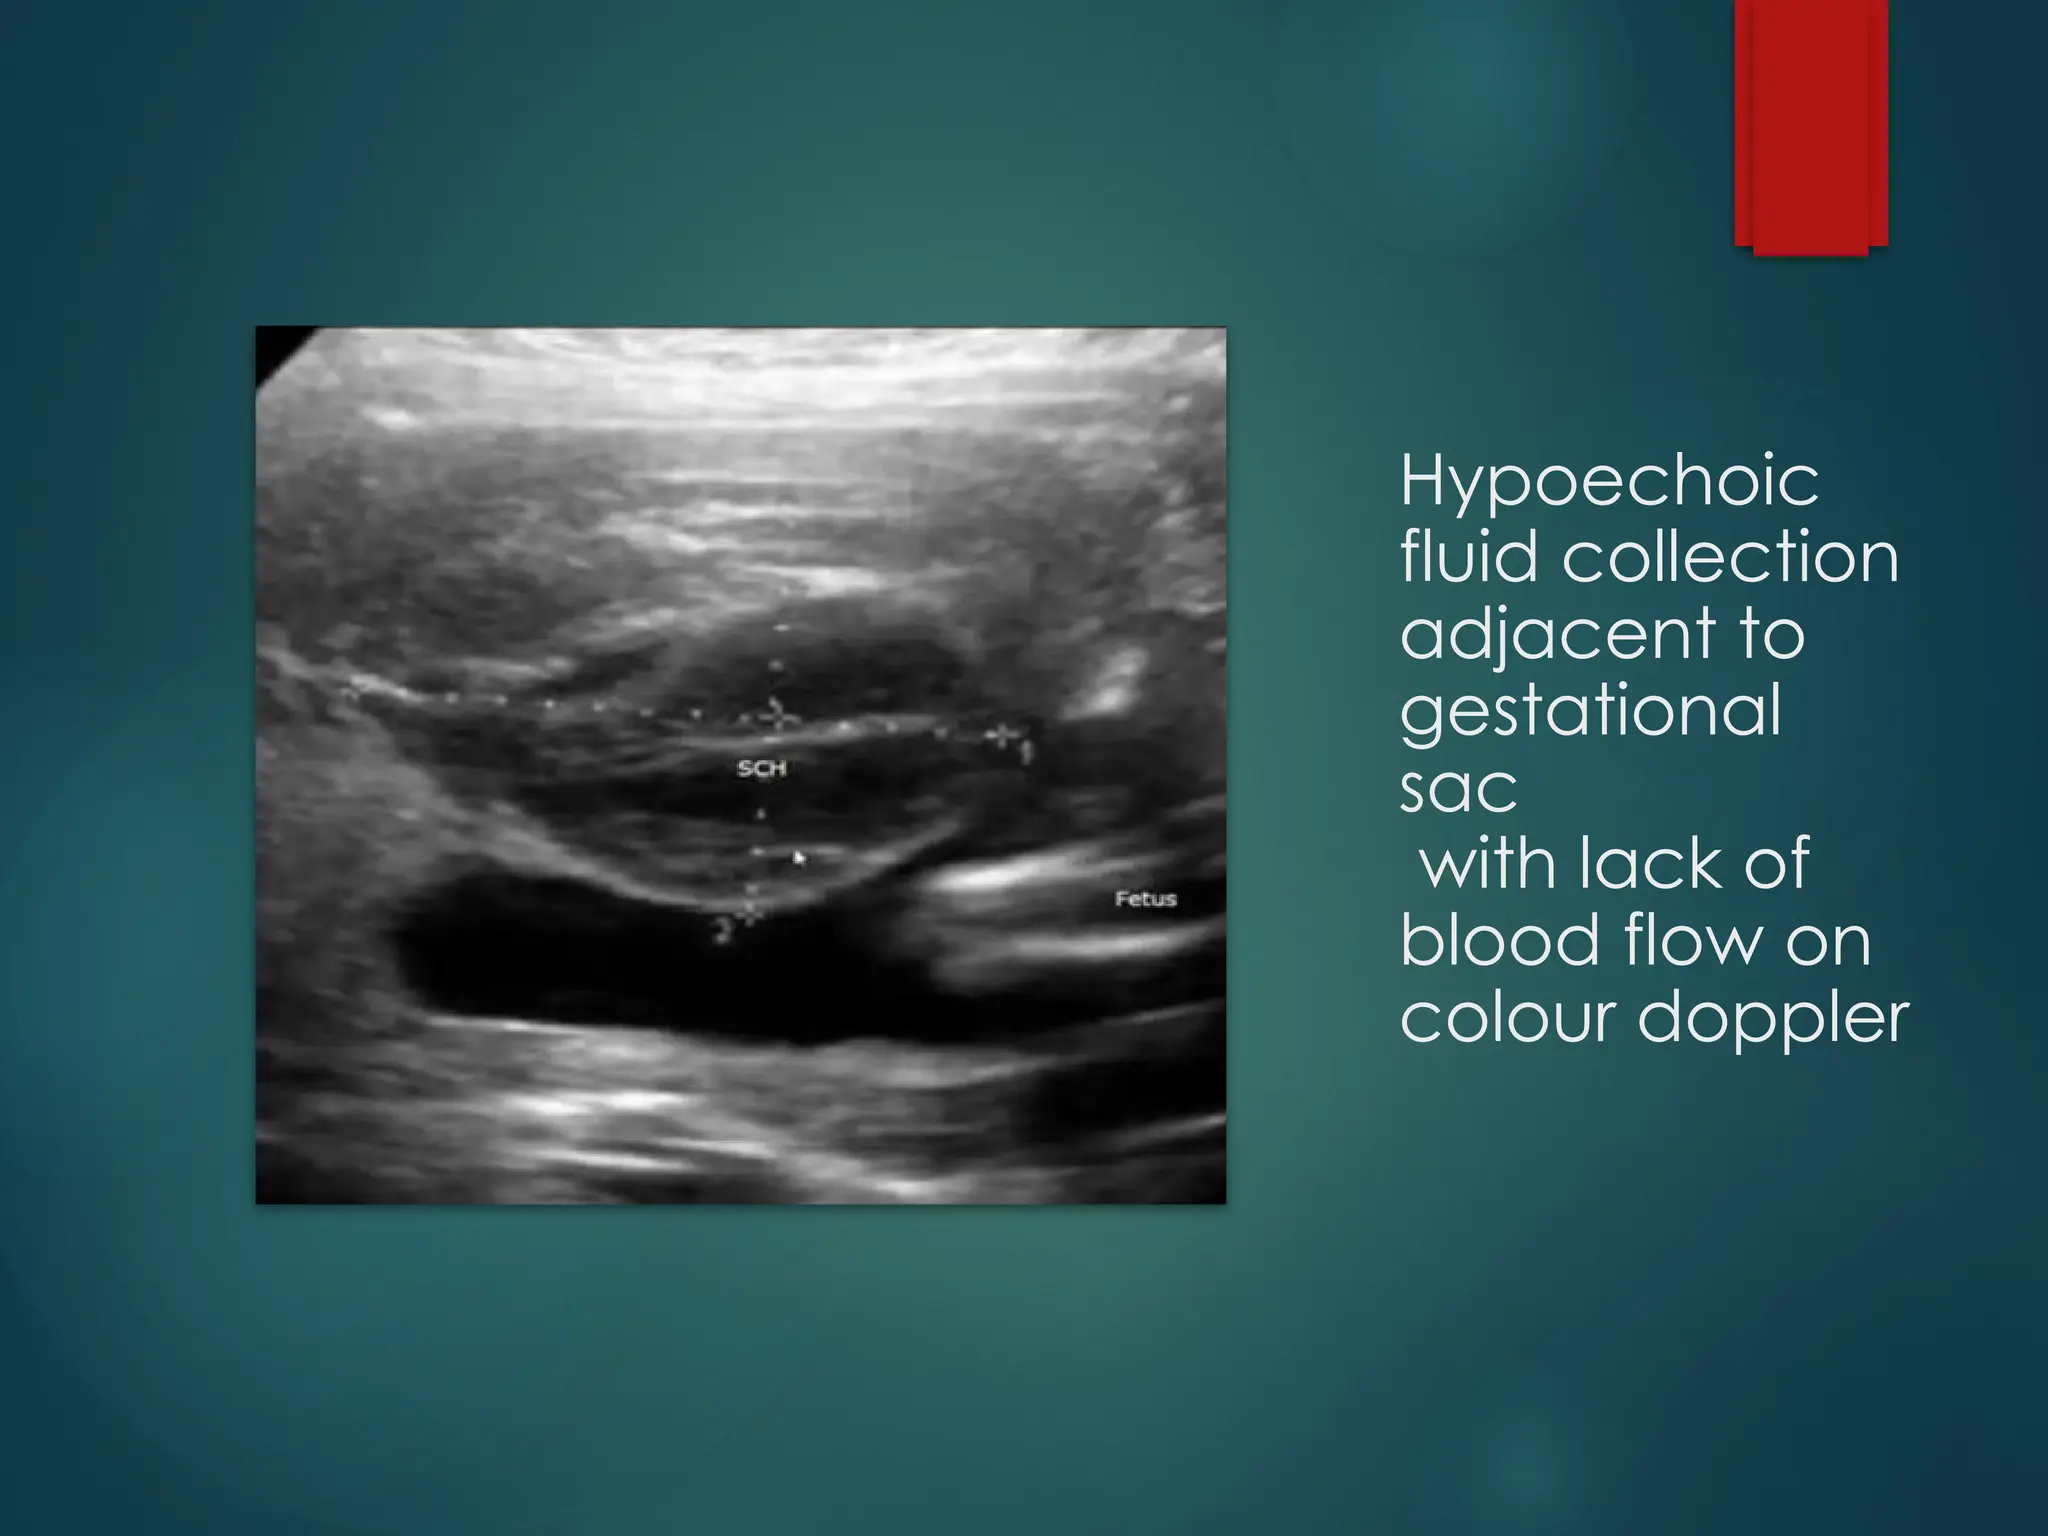

Hypoechoic

fluid collection

adjacent to

gestational

sac

with lack of

blood flow on

colour doppler

SUBCHORIONIC HAEMORRHAGE  Perigestationalhaemorrhage and blood collection outsidre the gestational sac that accumulates between the uterine wall and the chorionic membrane in pregnancy  Frequent cause of bleeding in first trimester and second trimester  Causes: Trauma, maternal conditions(clotting disorders, hypertension, hormonal changes, infections/inflamations, previous H/O SCH

HYPOECHOIC CRESCENT SHAPEDFLUID COLLECTION ADJACENT TO THE GESTATIONAL SAC